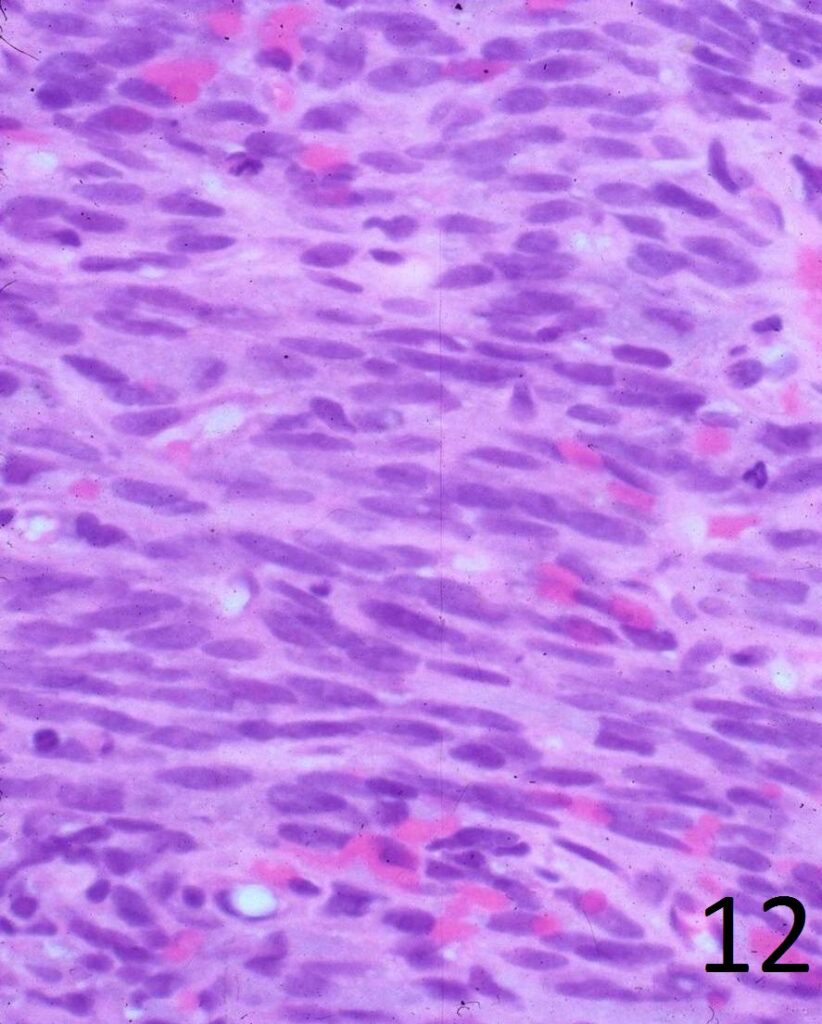

• Elongated, fairly uniform spindle cells with scant cytoplasm in a fibrous stroma

• Large nuclei with abnormal mitoses present; Higher grade tumors have more mitoses, necrosis and pleomorphism.

• Minimal pleomorphism with low grade tumors; More pleomorphism and mitoses with higher grade tumors

• Herringbone pattern (fascicles that intersect at right angles) (Fig. 11)

• Nuclei appear elongated with round ends (Fig. 12)